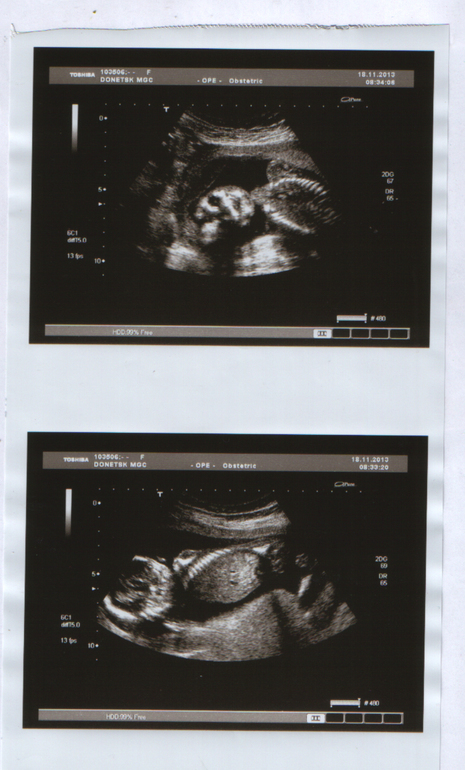

2 скрининг 17 недель и 6 дней)

Ну и немножко размеров наших) под катом)

БПР - 40 мм

ОГ -146,1 ( не знаю что это)

Грудь - 118 мм

Живот - 125 мм

Бедро - 26 мм

Стопа - 26 мм (прикольно что такая же как бедро))))))))

.плечо - 25 мм

Сердечко - 147 уд.

Так и опережаем по размерам на 2 денька)

А еще сказали весит наше счастье уже 220 г))))))

Дитятко наше и гладил себя по голове))) и переворачивался) А сфоткать нормально не дал врединка)

Ну и вот наш Тимофей!